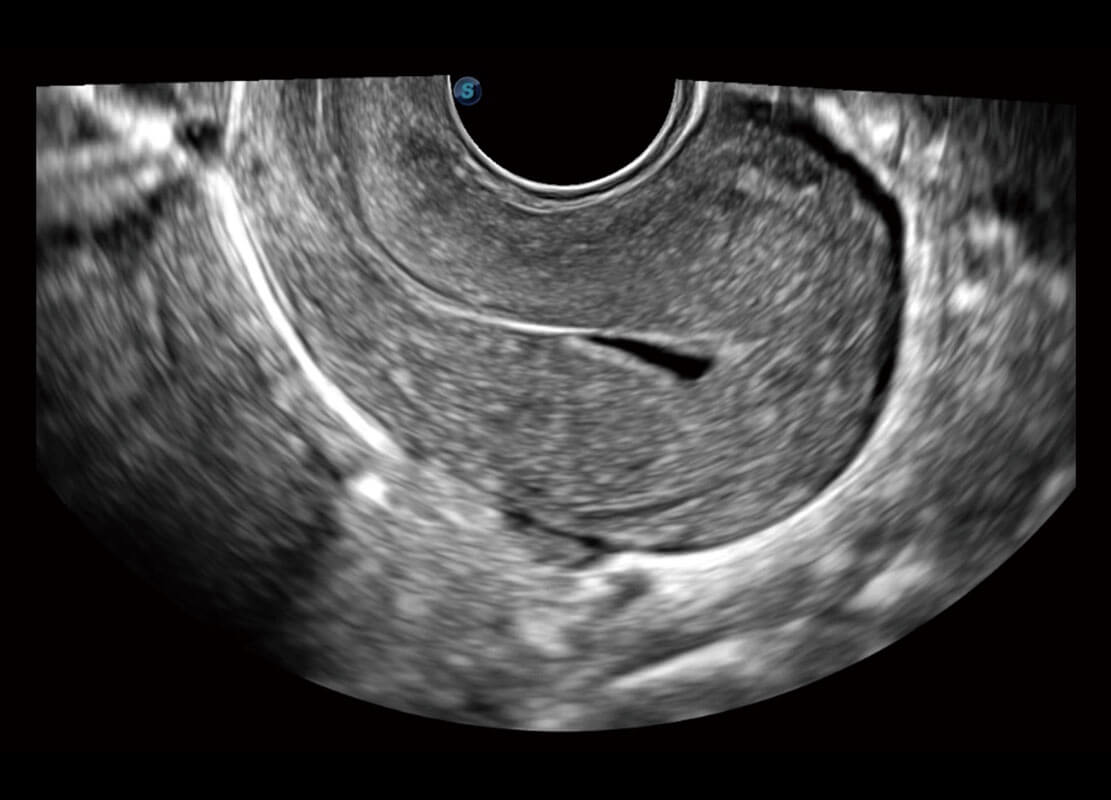

P60优异的图像质量搭载专科探头,在妇科基础疾病的诊断、卵泡生长的监测、输卵管通畅情况的判别等方面为您提供生殖应用方案。

腔内妇科-宫腔分离

腔内妇科-卵巢